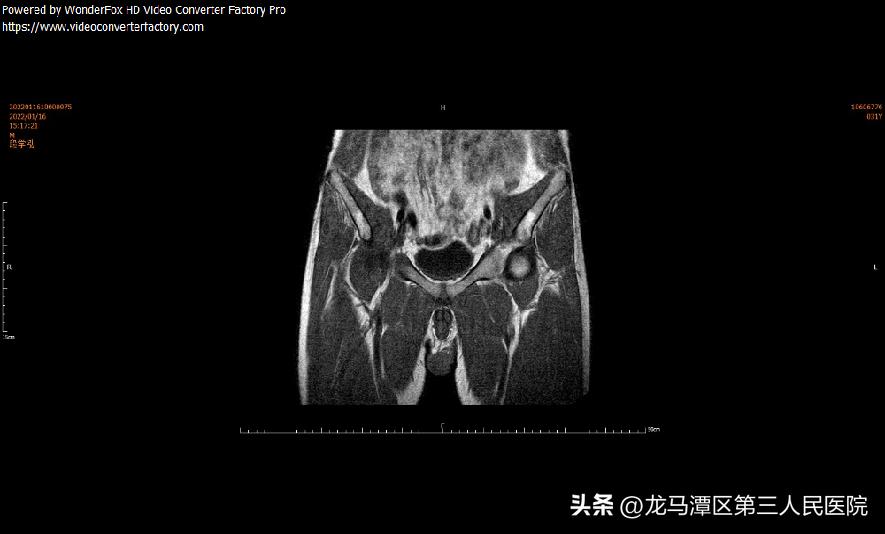

21年核磁随访

股骨头缺血性坏死不单是骨质的改变,也包括股骨头软骨软化、碎裂、游离体、滑膜增生肥厚等。髋关节镜主要针对于股骨头塌陷前(Ficat 分期I~Ⅲ期)。

对于年龄较轻、早期病变和保守治疗无效的患者,早期采取小直径,低转速,多孔道不同方向的钻孔减压和髋关节镜下清理术+自体造血干细胞移植,为较理想的选择。可有助于减轻关节疼痛,改善功能,延缓病情发展。